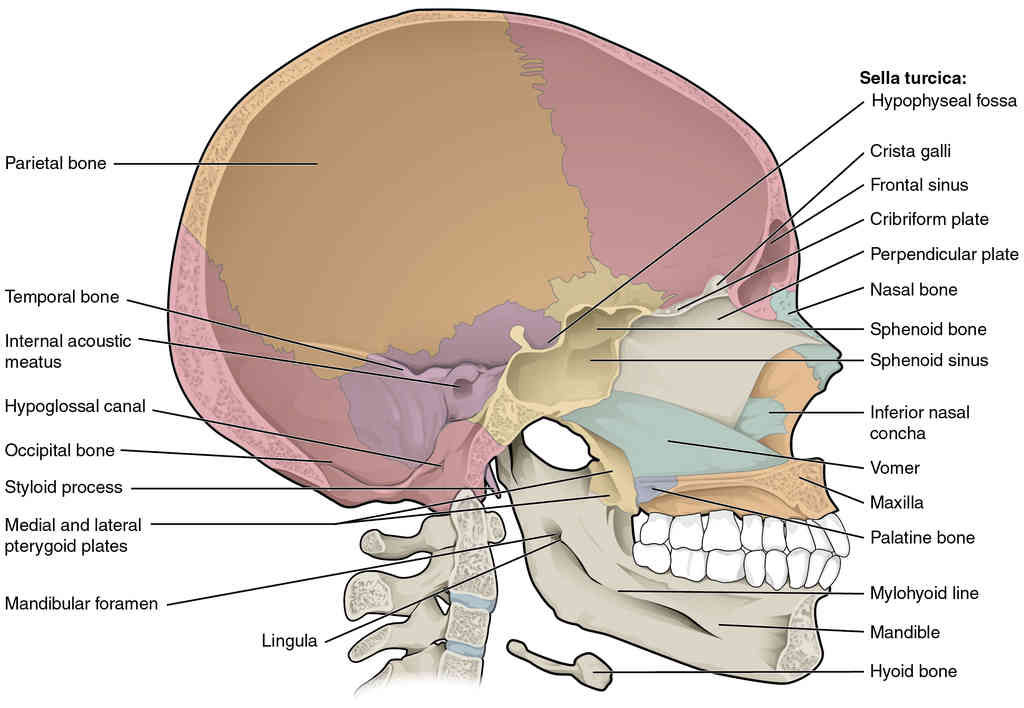

This page is under construction. For now, it is just a resource of the images found in the OpenStax Anatomy and Physiology Handbook. It wil slowly change into a revision tool. Each slide has a number. Use this to refer to the slide. When completed, it will have an unlabelled section, with labelled slides in parallel. On the unlabelled slides, write your answer and use the labelled slide to assess yourself. Keep track by also noting the number on each slide. Improvement at each attempt is important, more so than full marks on a first attempt.